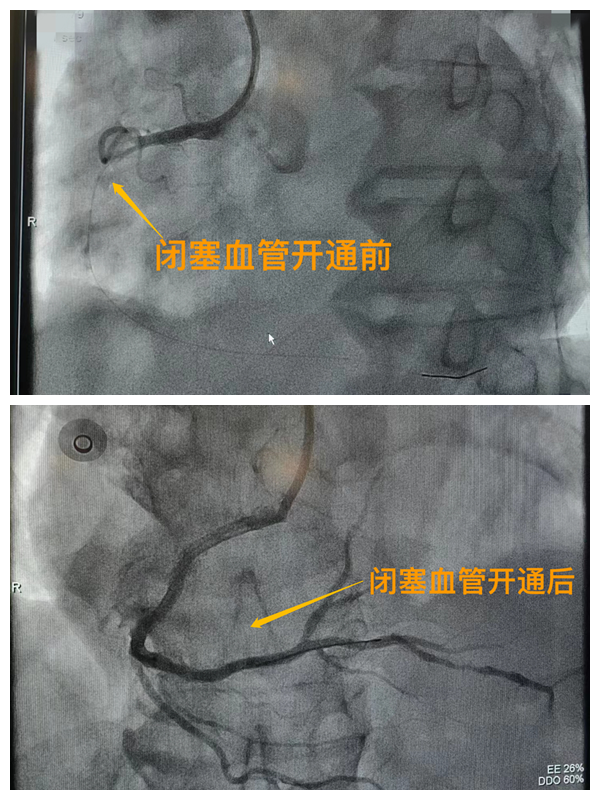

活動開始前,院長王瑾對現(xiàn)場群眾進(jìn)行了健康科普宣講,她以近期醫(yī)院救治的多例急性心肌梗死患者的癥狀、發(fā)展、急救、手術(shù)、康復(fù)全流程情況為例,向小區(qū)群眾講述了心梗的發(fā)病癥狀和院前急救注意事項,以及要及時通過120送至專業(yè)的胸痛中心開展科學(xué)、規(guī)范的急救手術(shù)的必要性,講述了心?;颊咿D(zhuǎn)危為安的全過程,得到了廣大群眾的共鳴與好評。

市二院胸痛中心于2021年12月23日通過中國胸痛中心認(rèn)證,成為國家級胸痛中心,先后開展了冠心病的介入診療、心律失常的心內(nèi)電生理檢查及射頻消融治療、永久起搏器植入、先天性心臟病的介入封堵及臨時起搏器植入、主動脈內(nèi)球囊反搏治療等,完成心臟介入手術(shù)3000余例。多次創(chuàng)造從入院至行急診介入手術(shù)開通血管(入門-導(dǎo)絲通過)30分鐘以內(nèi)記錄,極大保證了患者的生命安全,提高了預(yù)后質(zhì)量,挽救了眾多急性心?;颊叩纳?。(尹紅婭       張   靜)